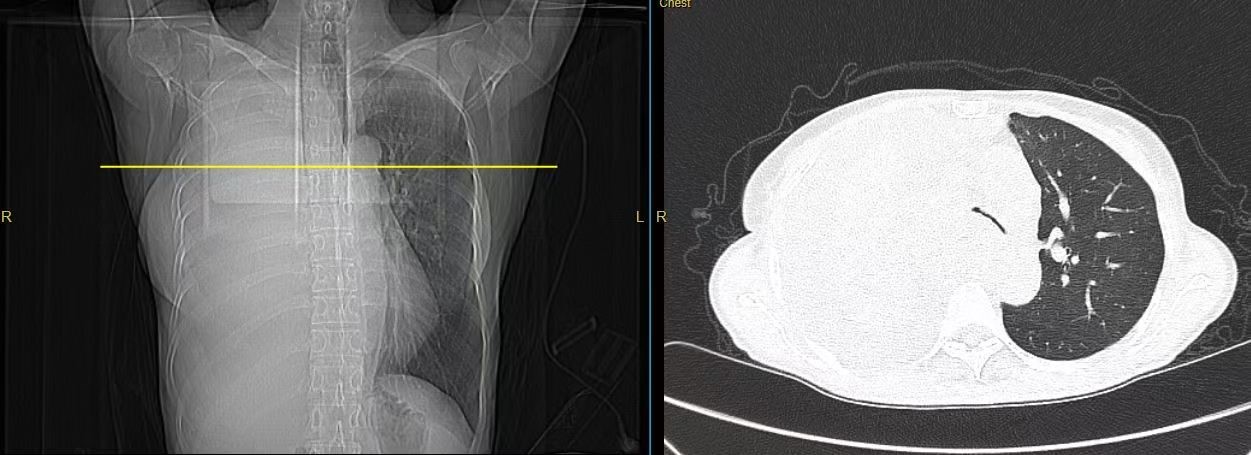

患者入院后,急诊血气分析提示严重的呼吸性酸中毒:PCO2高达82.6mmHg(正常值为35-45mmHg),PH值仅为7.274(正常值为7.35-7.45),患者已处于极度缺氧状态,随时可能停止呼吸。蒋军红主任团队迅速展开抢救,为患者实施气管镜下主支气管支架置入术。

术中发现,右主支气管完全闭塞,肿瘤新生物广泛浸润;左主支气管混合性狭窄,狭窄率高达70%,并伴有黏膜浸润样改变。团队冷静而高效地操作,仅用不到1分钟便将支架精准置入目标位置。置入的可过活检孔道气管支架成功打开了左侧主支气管,同时确保上下叶开口通畅。患者呼吸困难立即减轻,胸闷气促的折磨被迅速解除。术后,丁女士激动地拉着蒋军红主任的手,激动着说:“已经三天三夜没能躺下睡觉了,谢谢你们让我又能喘口气!”